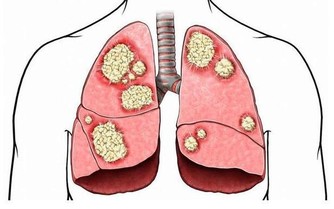

乙肝在亞非國家相當普遍,很多人也對乙肝比較重視,乙肝的傳染性雖普遍存在,

但是目前對嬰幼兒、兒童構成威脅,我國的新生兒在出生時就會安排注射乙肝疫苗,所以目前來說乙肝病毒是很難有威脅了。而對於那些少數的乙肝病毒攜帶者在治療過程中

如果不注意護理就會導致病情惡化加重,所以患者要注意乙肝惡化的前兆症狀。

10種症狀說明乙肝正在惡化